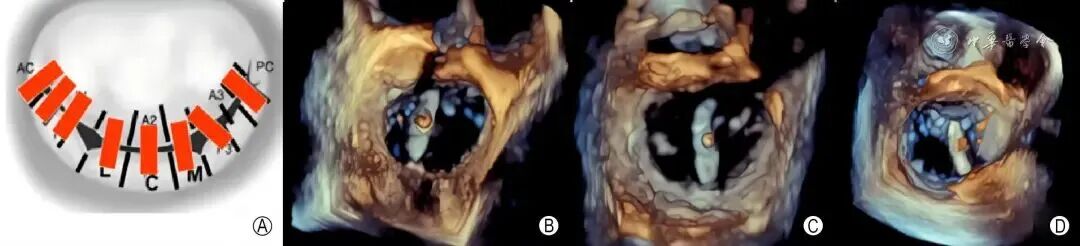

4. 3D影像评估二尖瓣病变

采用3D聚焦ZOOM模式获取二尖瓣“外科视野”立体显示二尖瓣前后叶,将主动脉瓣置于屏幕顶部12点钟的位置,此时二尖瓣内、外交界应处于平齐状态,左心耳在大约9点钟的位置,结合3D彩色多普勒超声可以更加准确地评估MR的部位、机制及程度,帮助制定手术策略(图4)。

图4 三维外科视野显示二尖瓣后瓣脱垂导致重度二尖瓣反流 A:经食管超声心动图三维外科视野显示二尖瓣后叶P2区脱垂;B:三维外科视野结合彩色多普勒超声模式显示二尖瓣后叶P2区脱垂引起的重度二尖瓣反流